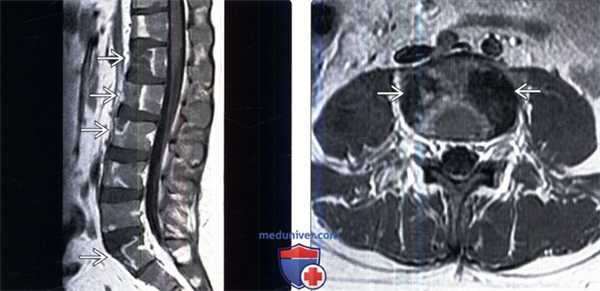

(Слева) Сагиттальный срез, Т1-ВИ с КУ, пациент с вновь установленным диагнозом лимфолейкоза: множественные четкие фокусы сниженного накопления контраста в телах позвонков. ограниченные зонами усиленного контрастирования. Мягкотканных образований в паравертебральной области или изменений межпозвонковых дисков не определяется.

(Справа) Аксиальный срез, Т1-ВИ с КУ, пациент с множественными инфарктами тел позвонков и вновь установленным диагнозом острого лимфобластного лейкоза: четко ограниченные очаги в боковых отделах тела позвонка с минимально выраженным контрастным усилением по периферии.в) Дифференциальная диагностика:

(Слева) Сагиттальный срез, Т1-ВИ: множественные инфаркты тел позвонков у пациента с острым лимфобластным лейкозом после проведенной химиотерапии. Обратите внимание на четко ограниченные зоны низкой интенсивности сигнала в передней половине тел позвонков.

(Справа) Сагиттальный срез, FS Т2- ВИ, этот же пациент: четкие зоны высокой интенсивности сигнала в передних половинах тел позвонков, аналогичные изменения видны в области крестца.г) Патология. Макроскопические и хирургические особенности: